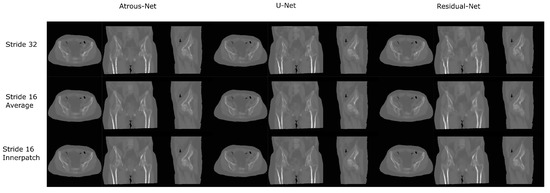

3.2. Pelvis Dataset Results

The results for all tissues using the pelvis dataset are depicted in Table 16, Table 17 and Table 18; the results using only the bone voxels are detailed in Table 19, Table 20 and Table 21; the results using only the fat voxels are detailed in Table 22, Table 23 and Table 24; and the results using only the soft-tissue voxels are detailed in Table 25, Table 26 and Table 27. In the pelvis dataset all networks performed very similar when all tissues were considered. However, 3D networks obtained slightly worse results when assessing bone alone and very similar results for all tissues. The best network in the bone dataset was the 2D Residual network that obtained a MAE of 201.56 HU, a PSNR of 23.20 and a Pearson Coefficient of 0.476 in the bone. Additionally, the error in bone with all networks increased when the 3D scheme was used. The ANOVA test for the 2D results reported a statistically significant effect of the networks in all tissues and bone MAE (all tissues: F 2 , 56 = 6.7 , p < 0.005 ; bone: F 2 , 56 = 8.5 , p < 0.001 ) and PSNR (all tissues: F 2 , 56 = 8.5 , p < 0.001 , bone: F 2 , 56 = 5.3 , p < 0.01 ). According to 3D results, the ANOVA test did not expose statistically significant differences when using different architectures on all tissue MAE (all tissues: F 2 , 56 = 2.3 , p = 0.10 ; bone: F 2 , 56 = 6.2 , p < 0.005 ) and PSNR (all tissues: F 2 , 56 = 1.4 , p = 0.25 ; bone: F 2 , 56 = 4.3 , p < 0.05 ). Post hoc Student’s t-test is depicted in Table 28 and Table 29. It reveals that the Residual-net and Atrous-net did not provide statistically significant differences. Visual result examples of pelvis pseudo-CTs are depicted in Figure 8 and Figure 9. Table 30 shows the time needed to synthesize a whole pelvis volume using the different architectures.

Figure 8. Pelvis results using 2D networks.

Applsci 12 11600 g008

Figure 9. Pelvis results using 3D-16 networks.